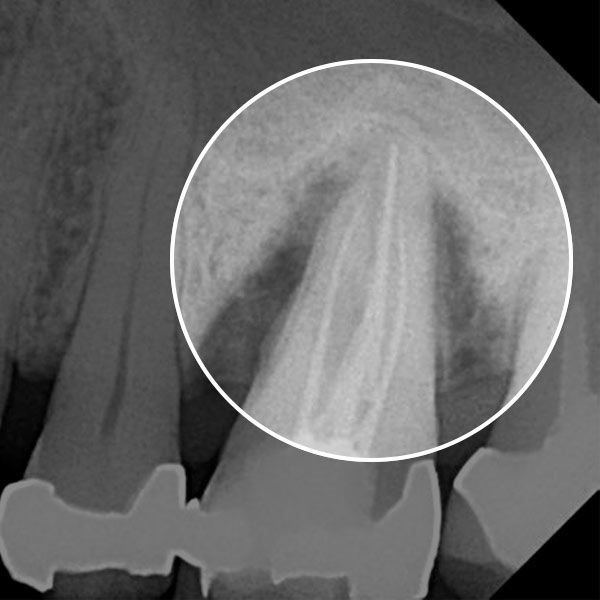

Advanced gum disease can lead to cavities, tooth loss, and a variety of other dental concerns. If you have advanced gum disease, LANAP® laser gum surgery is an FDA-cleared method for encouraging gum tissue reattachment and regenerating bone tissue. LANAP is unique because it can target diseased tissue without removing healthy tissue and decrease the depth of periodontal pockets.